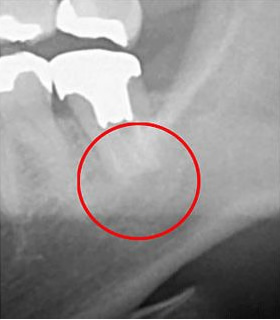

根管は狭く複雑で、目に見えない部分に存在します。当院では、根管の形状を正確に把握するために「CT」を利用しています。CTは360度回転しながら撮影を行うため、立体的かつ鮮明な画像を提供します。以下に、CTと従来のレントゲン撮影の画像比較を示します。

同じ患部をCTで撮影したもの(左)と、レントゲンで撮影したもの(右)です。CTで撮影した黒い影は、炎症を示していますが、レントゲンで撮影したものには炎症は見られません。

CTでしか確認できない初期の炎症も見逃さずに、より精密な診断を行うことができます。